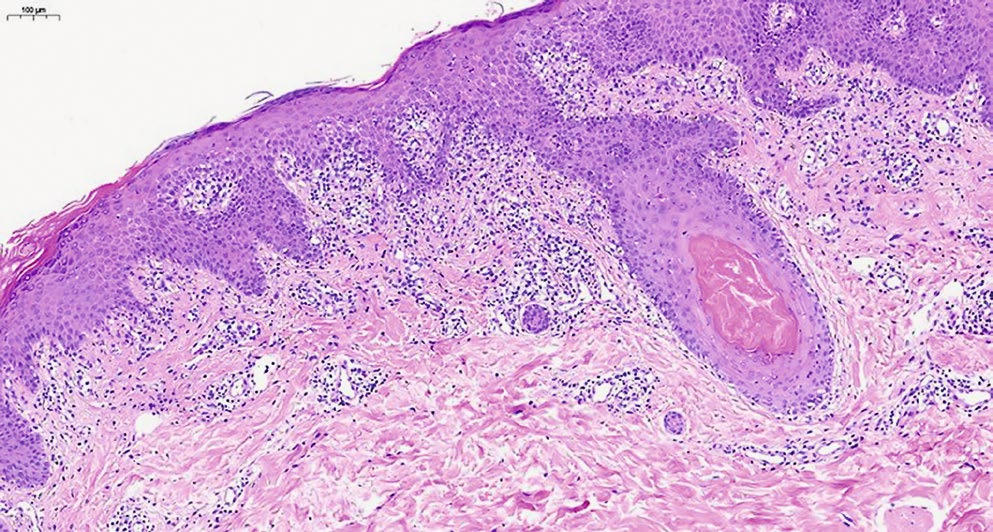

При гистологическом исследовании фрагмента кожи с окраской гематоксилином и эозином выявлен эпидермис с нерегулярным слабо выраженным акантозом, признаками чередования участков пара- и ортокератоза, перифолликулярными участками паракератоза, корками на поверхности, фолликулярными кератиновыми пробками (рис. 2). В верхних слоях дермы обнаруживается периваскулярный лимфогистиоцитарный инфильтрат с участками выраженного эпидермотропизма, в проекции которых эпидермис демонстрирует выраженный спонгиоз (рис. 3), признаки вакуольной дистрофии, содержит многочисленные тельца Сиватта (рис. 4). Среди клеток инфильтрата видны мелкие фрагменты коллагеновых волокон. Кровеносные сосуды сосочкового слоя дермы расширены, придатки кожи сохранены.

Рис. 2. Изменения в эпидермисе — акантоз, чередование участков пара- и ортокератоза, перифолликулярный паракератоз, окраска гематоксилином и эозином, ×100